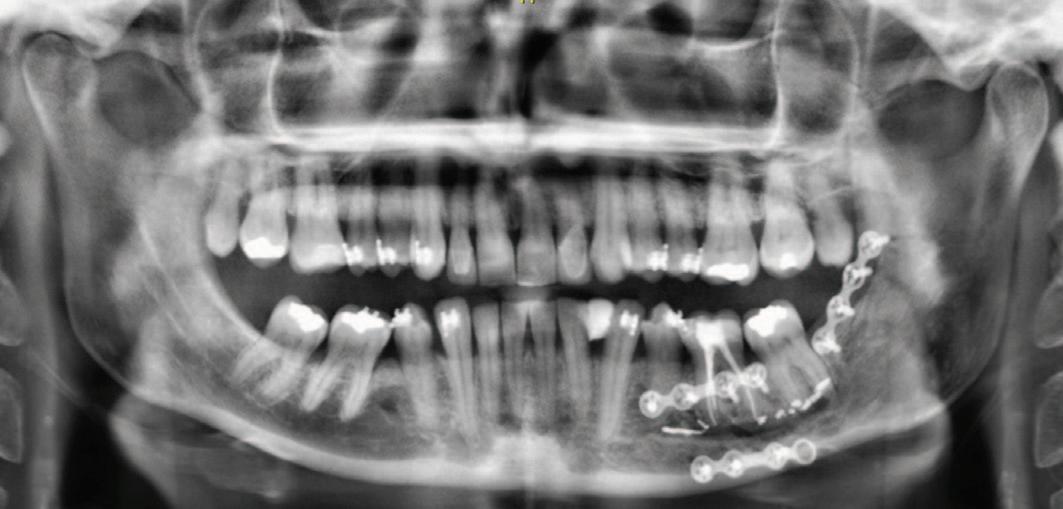

FIGURE 3: CBCT scan demonstrating the presence of the material inside the canal.

Radiographic examinations consisted of digital orthopantomogram (OPG), peri-apical (PA), and cone beam computed tomography (CBCT) scans. The scans revealed that the lower left first molar root canals were obturated with a radiopaque material, and showed root canal filling extending beyond the apices of the tooth and approximately 5cm along the mandibular canal ( Figures 1 , 2 and 3 ).